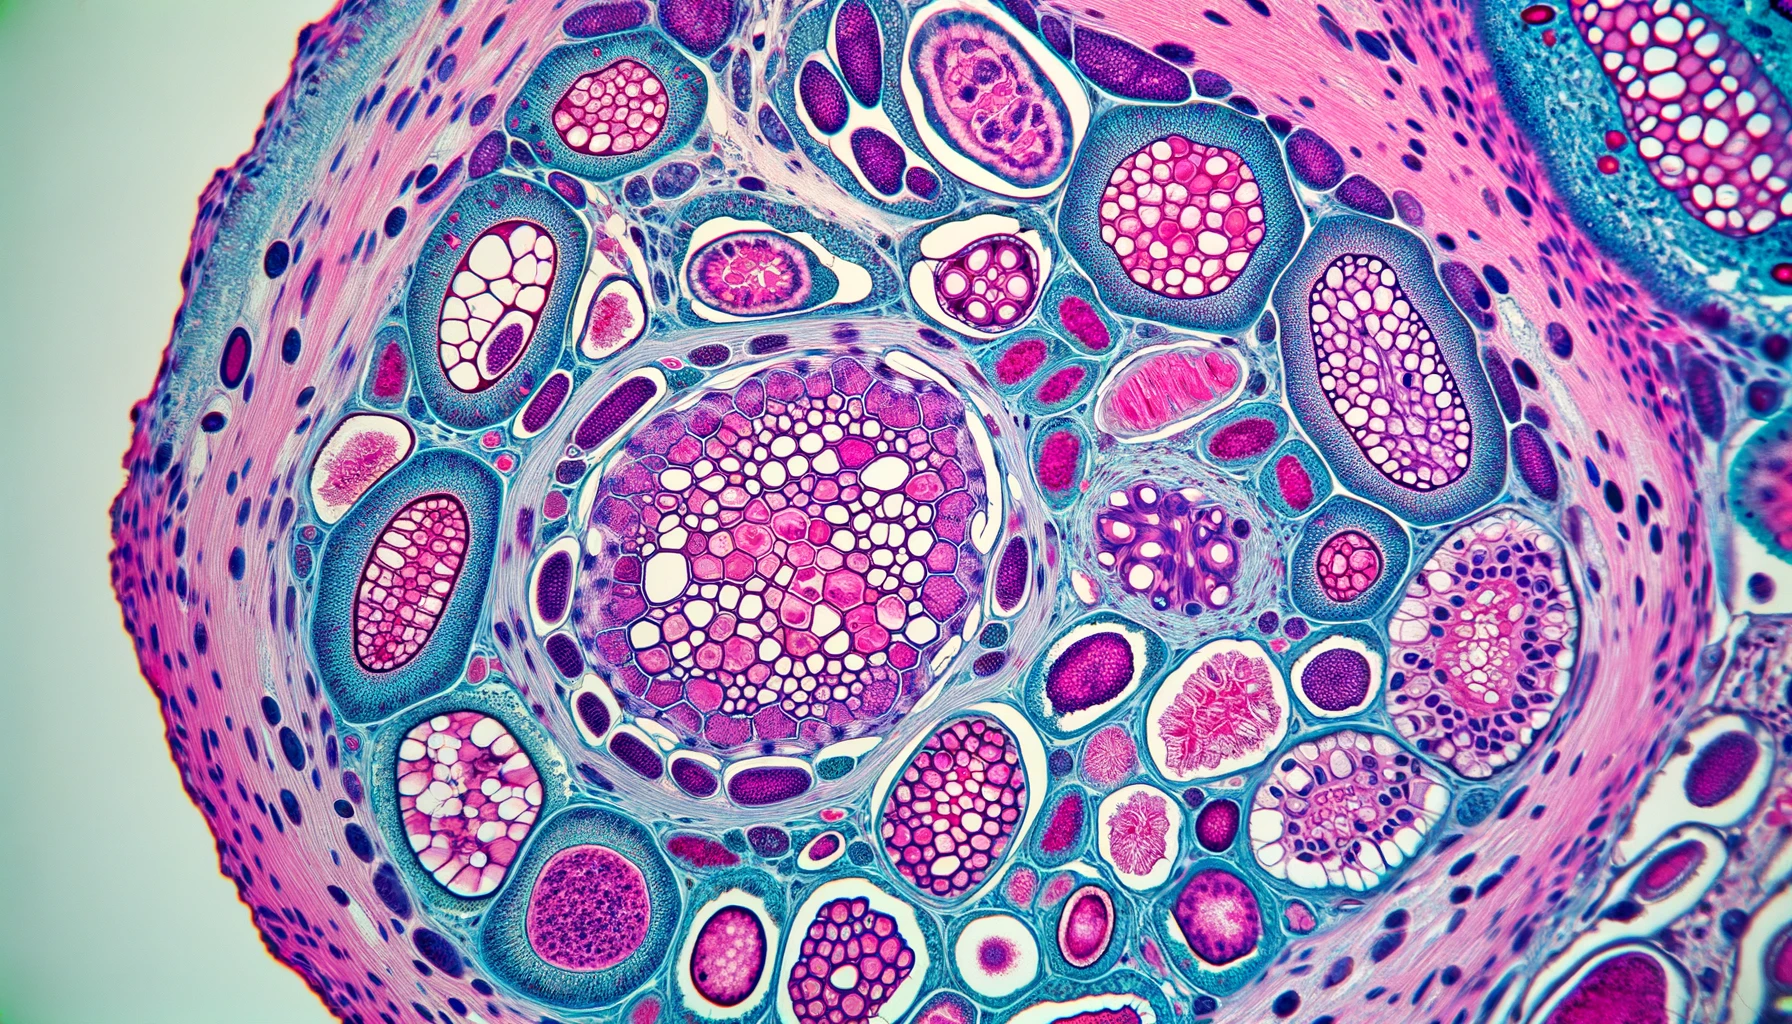

Focal Segmental Glomerulosclerosis (FSGS)

FSGS causes scarring in the kidneys, which can lead to protein loss and kidney failure. Clinical research is vital for discovering effective treatments. Patients participating in studies can gain access to cutting-edge therapies. Interested individuals are encouraged to click below to register interest in joining upcoming trials.

Membranous Nephropathy

Membranous Nephropathy involves damage to kidney filters, leading to protein leakage into urine and potential swelling. Clinical research plays a crucial role in advancing treatment for such conditions. By participating in clinical trials, patients can access new therapies that may improve their health outcomes.Interested individuals are encouraged to click below to register interest in joining upcoming trials.

IgA Nephropathy

IgA Nephropathy, characterized by IgA protein buildup in kidneys, can cause inflammation and impede kidney function. Our clinic is conducting 3 studies on this condition. Participating in clinical research means receiving top-tier medical care without any cost and being compensated for your time. It's an opportunity to potentially improve your condition and contribute to groundbreaking medical research. To take part in this vital research, please click below to apply.